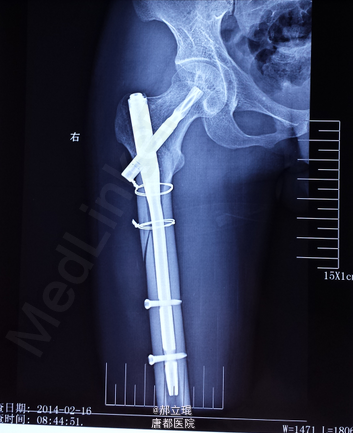

髓内钉

做髓内钉手术处理。

建议近期内不可负重,多吃高钙食品,多晒太阳,多锻炼。近三个月时患者肢体康复。